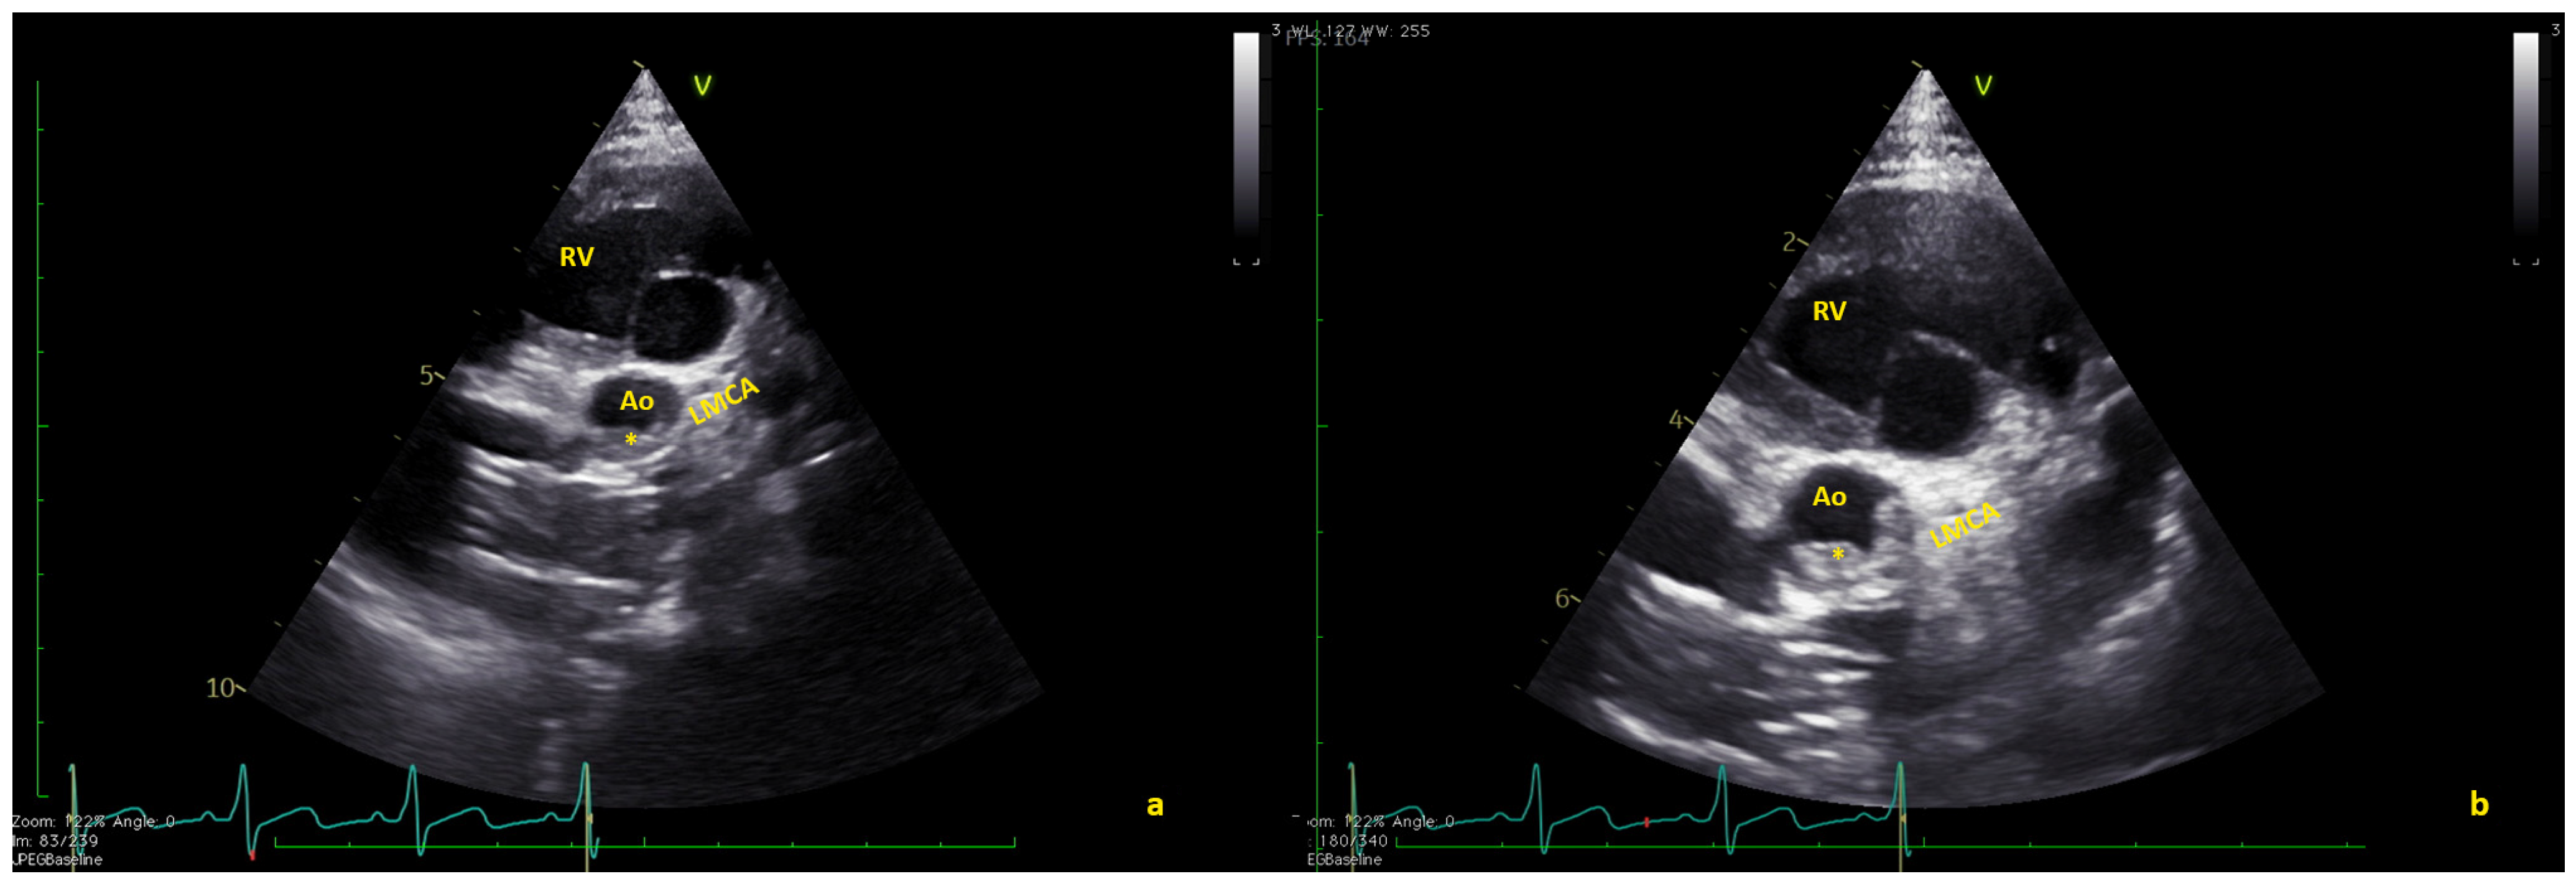

Figure 2.

(a) Short axis view showing the thrombus (*) in native aorta (Ao). (b) In some frames, the thrombus seems to partially obstruct the coronary arteries. LMCA = left main coronary artery; RV = right ventricle (Video S2).